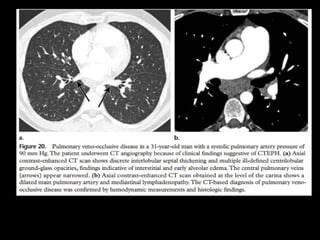

HAP pós-capilar

Doença pulmonar venoclusiva

Definição: trombose venosa pulmonar com sinais e

sintomas de HAP;

Associação com medicamentos(bleomicina e

mitomicina), HIV, TMO e sarcoidose;

Na adolescência a incidência é igual entre os sexos,

mas na fase adulta/velhice há discreto predomínio

de homens;

Patologia: estenose ou obliteração parcial das veias

e vênulas pulmonares por tecido fibroso

proveniente da íntima.